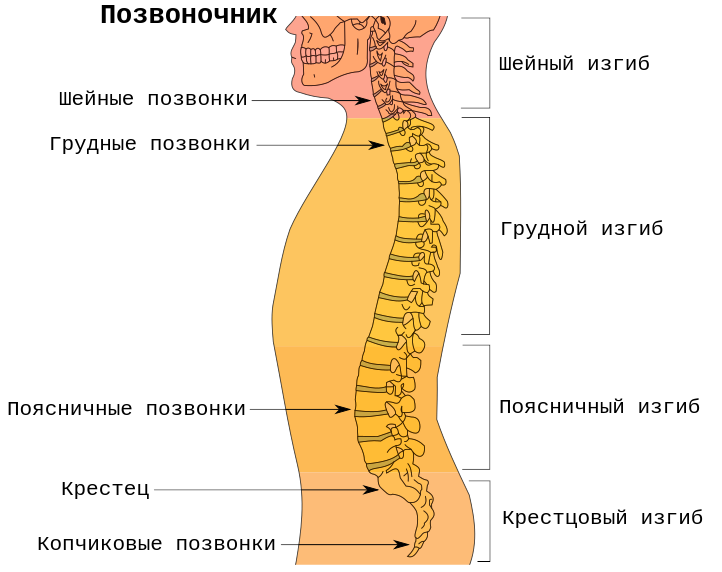

Структура позвоночника: сегменты и тазовые отделы в фотографиях

Раздел: Кадры перемен